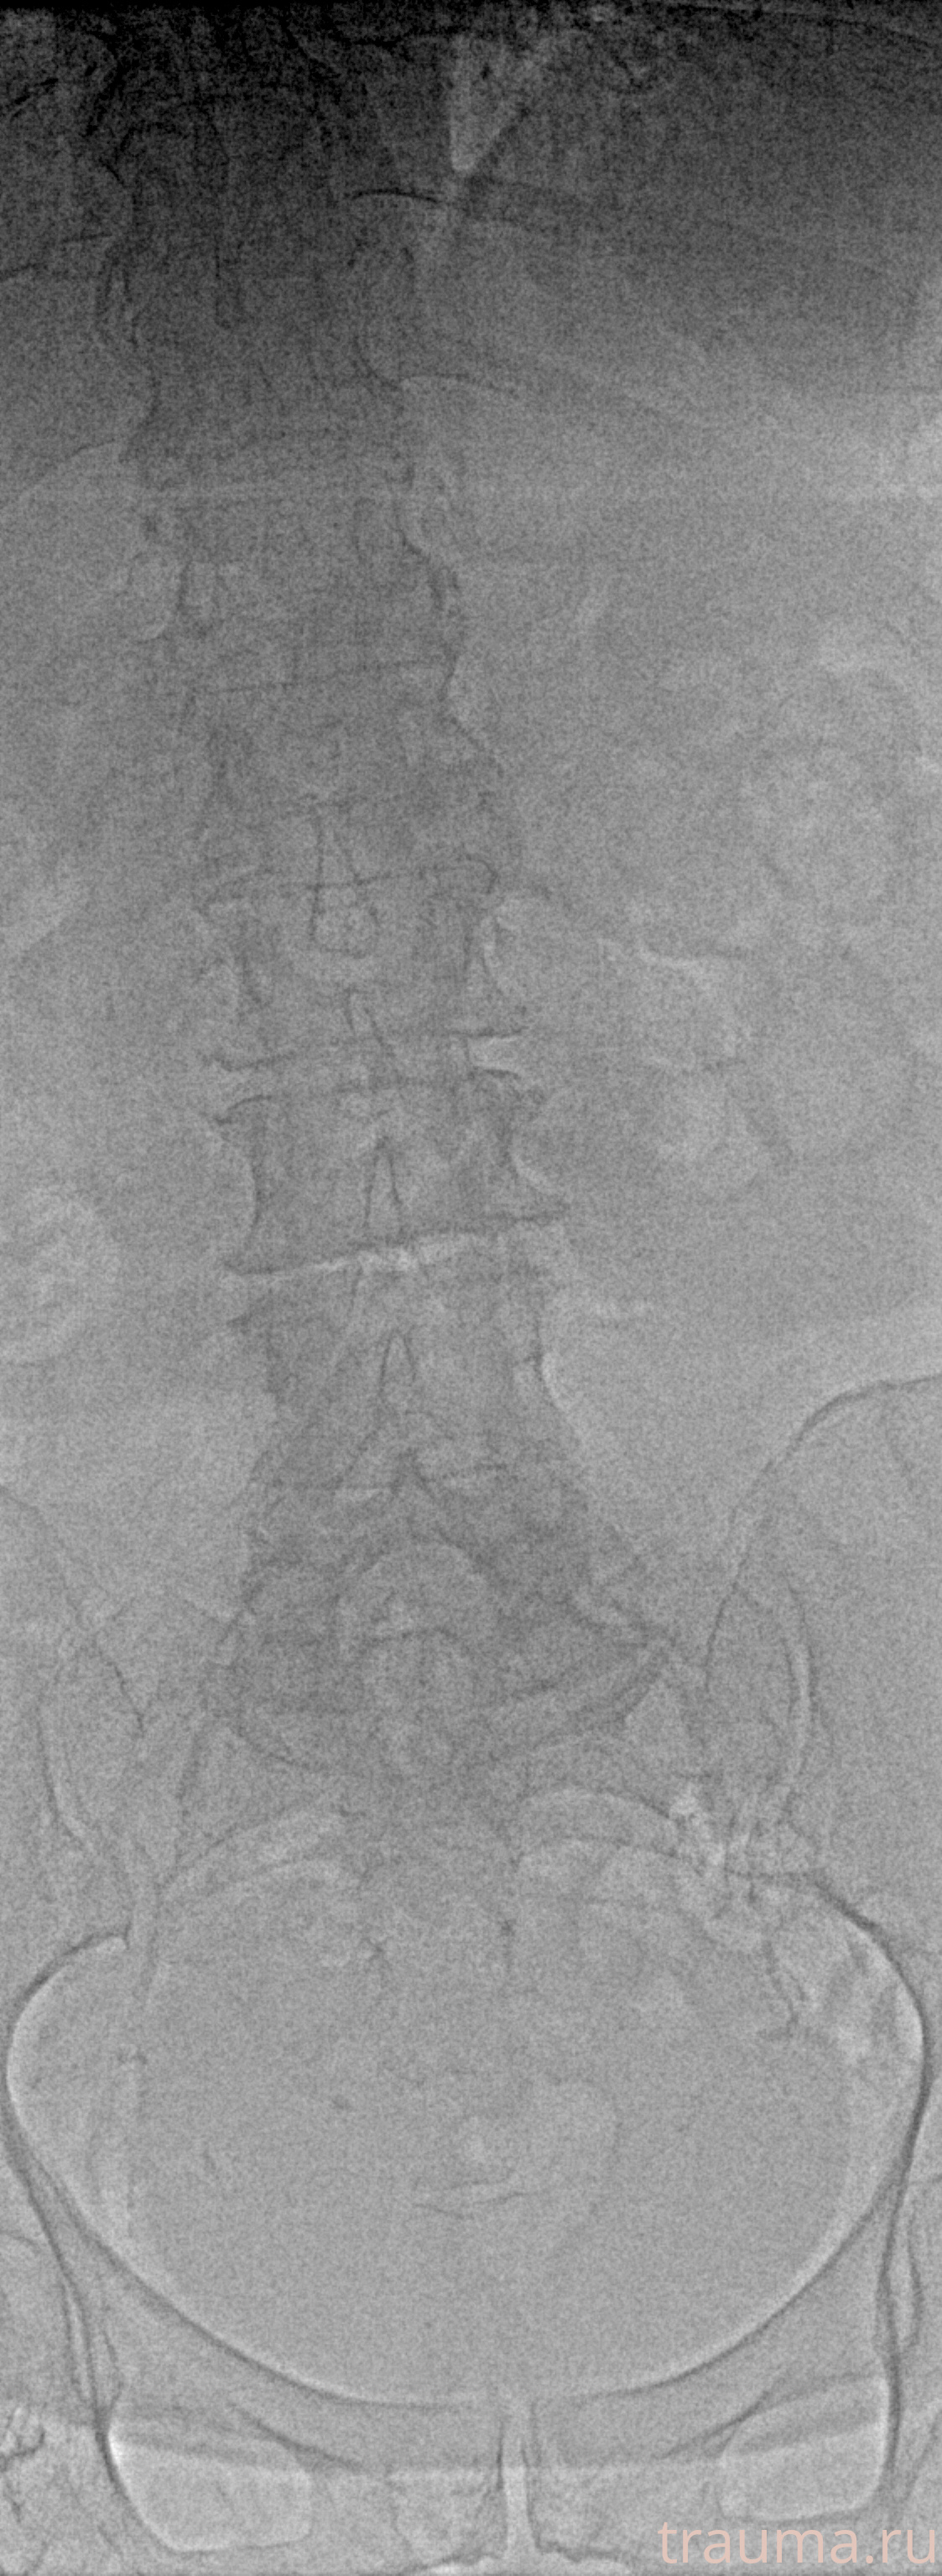

Рентгенограммы

Рентген на дому: по вашему адресу приезжает врач-рентгенолог, травматолог-ортопед с мобильным рентгеновским аппаратом, проводит диагностику травмы или заболевания, делает необходимые рентгенограммы, дает рекомендации по дальнейшему лечению. Получить качественные снимки в домашних условиях возможно благодаря уникальной методике, разработанной МосРентген Центром для института  Склифосовского